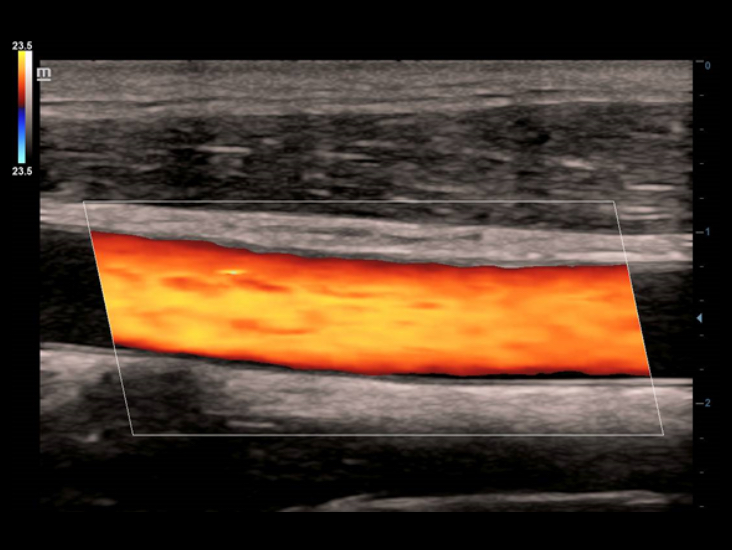

ComboWave transducers

In tegenstelling tot traditionele transducers gebruiken de ComboWave-transducers een nieuw type samengesteld pi?zo-elektrisch materiaal om het akoestische spectrum drastisch te optimaliseren en de akoestische impedantie te verminderen. De lineaire transducers van ComboWave, die verder zijn ge?ntegreerd met de unieke 3T-technologie van Mindray, stellen u in staat uitstekende prestaties te ervaren met een extreem hoge beeldresolutie en uniformiteit in de schildklier, borst, vaten en meer.

Smart Track biedt snelle en intelligente optimalisatie voor vasculaire beeldvorming met slechts ├®├®n druk op de knop. Het optimaliseert het kleuren-, power- en PW-spectrum met zelftracking en reduceert het aantal tijdrovende stappen. De workflow voor vasculair onderzoek wordt daarmee vereenvoudigd met een optimale weergave.